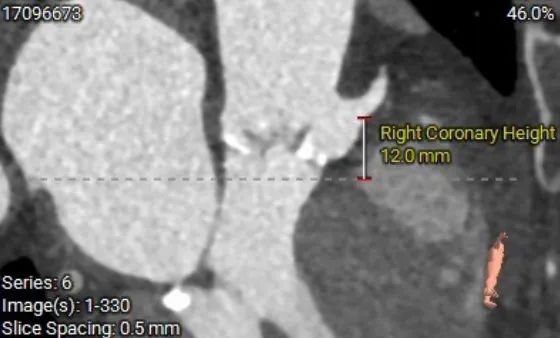

冠脉高度测量

RIGHT CORONARY

右冠开口高12.0mm